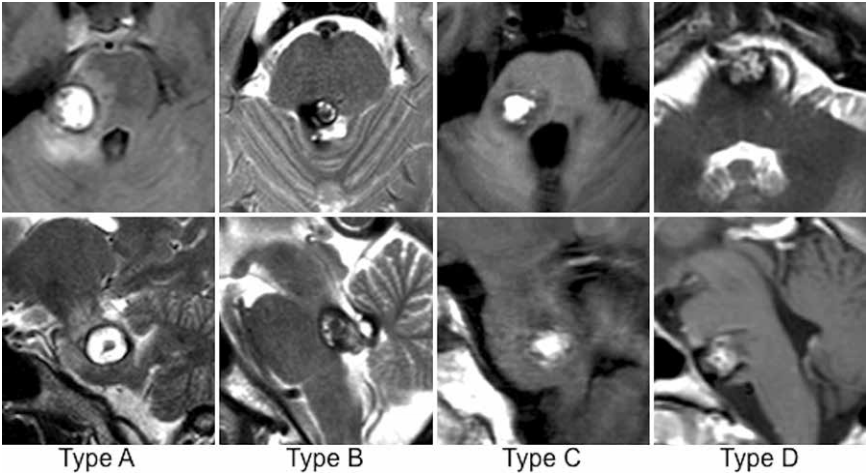

INC巴特朗菲教授在此论文种还根据最合适或可能的手术入路定义了4种不同病变类型(A-D型)桥脑海绵状血管瘤。每列显示一名具有代表性桥脑海绵状血管瘤类型患者的轴向(上)和矢状(下)MR图像。

A型病变:只有脑桥后外侧入路似乎合理且适合进入桥脑海绵状血管瘤A型病变,因为病变与脑桥的侧面邻接,并且距离菱形窝相当远。从脑桥内侧入路受侵犯受,具有显著且不合理的脑干实质损害。

B型病变:只有一条脑桥后内侧的入路似乎是合理的,适合通过B型桥脑海绵状血管瘤,因为病变是位于距桥脑外侧表面相当远的位置,但足够接近或甚至突出菱形肌颅窝进入第四脑室。从横向入路可能造成脑干实质损伤。

C型病变:脑桥后外侧入路或脑桥后内侧入路被认为是可能的,并且两者都是同样有效的选择,被选为C型桥脑海绵状血管瘤病变的通路。自从病变位于桥脑外侧表面之间和菱形窝,很可能是从任何一侧,预计每种方法都可能产生可比较的手术结果;两者都不方法似乎明显优于其他方法。

D型病变:对于D型桥脑海绵状血管瘤,只暴露有前外侧桥脑是较为合理的,因为脑桥的主要部分或整个病灶位于桥脑冠状中线前方。本系列中桥脑海绵状血管瘤的脑桥后外侧入路,开颅可通过外侧幕下小脑上、乙状窦后、远外侧髁和远外侧入路方法实现。桥脑海绵状血管瘤的脑桥后内侧入路是枕下正中开颅术